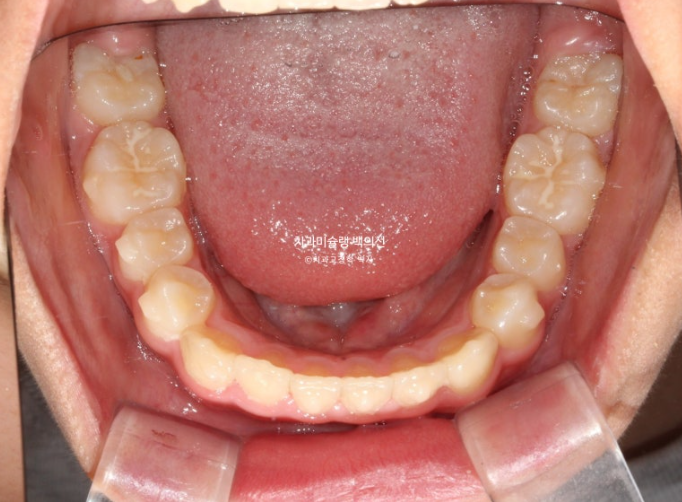

교합과 아래배열은 완벽하게 유지되고 있습니다.

25년 5월부터 25년 7월까지 앞니 배열 개선을 위해 추가장치를 짧게 낀 후 치료를 마무리 하였습니다.

25.07

중심선은 잘 맞으며

어금니 교합은 물샐틈 없는 1급 교합관계를 보입니다.